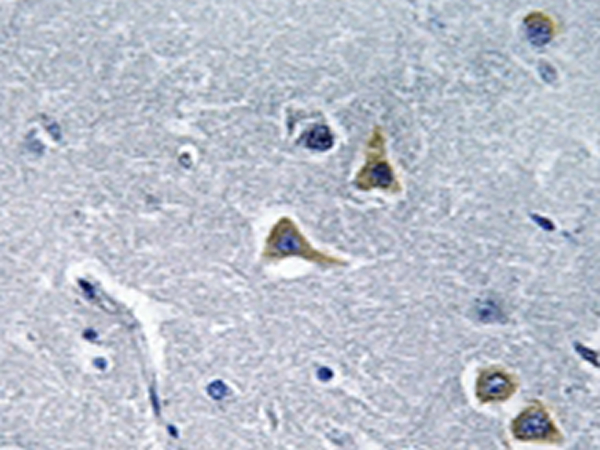

Applications: |

IHC |

IHC positive control: |

Human brain tissue |

IHC Recommend dilution: |

50-100 |